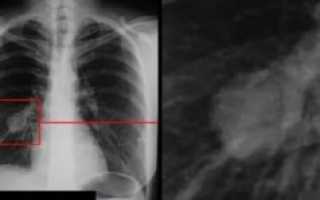

Диагностика онкологических заболеваний на ранних стадиях даёт возможность для назначения продуктивного лечения и увеличивает шансы на положительный эффект проведённой терапии. Определить рак легких на флюорографии (ФЛГ) в начале болезни удаётся при нахождении опухоли в наружных слоях ткани, а также при выполнении снимка в двух проекциях. На поздней стадии данная патология выявляется почти в 100 % случаев.

Ошибочно считать, что флюорограмма не показывает рак органов дыхания. Этот метод исследования используется для выявления структурных изменений в лёгочной ткани. Рентгенолог проанализирует рисунок тканей, обратит внимание на затемнения, пятна, уплотнения, изменения кровоснабжения участков.

Патологические признаки будут обнаружены, даже если их нельзя рассмотреть детально. При этом флюорография должна быть дополнена другими диагностическими процедурами. При обнаружении на флюорограмме затемнений нетипичного характера врач-онколог обычно рекомендует пройти компьютерную томографию.

Периферическая карцинома имеет вид «шаровидной» тени с размытым контуром, дорожкой к корню. Этот вид роста карциномы чаще диагностируется на ранней стадии.